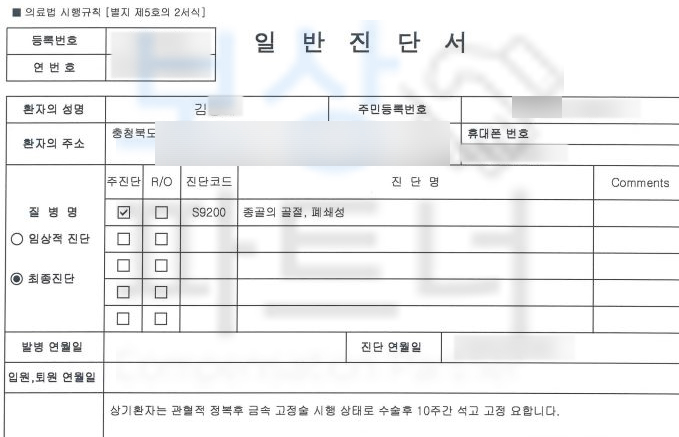

실제 진단서를 보실까요?

종골의 골절, 폐쇄성 S9200 진단을 받았습니다. 위 병명으로 김@@님은 관혈적 정복 후 금속 고정술 시행받았고 10주간 석고 고정 진단을 받았습니다. 먼저 일하다 다친 사고이기에 의무 가입인 산재 보험에서 치료비와 일을 못하는 기간에 대해 보상을 받을 수 있습니다.